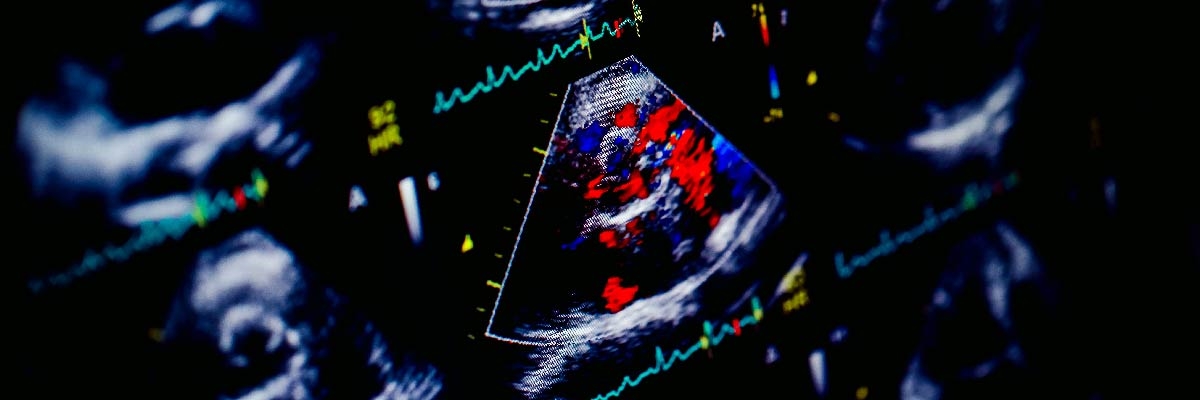

Renkli Doppler Ekokardiyografi

Renkli doppler ekokardiyografi sırasında hastalarda herhangi bir semptoma neden olmayan, zararsız kontrast madde kullanılır. Bu madde taramada net bir şekilde görülür ve kalbin daha iyi bir görüntüsünün alınmasına yardımcı olur.

Doppler ekokardiyografi genellikle transtorasik ve transözofageal ekokardiyografiye yardımcı olması amacıyla kullanılır. Geleneksel ultrasonun algılayamadığı kalp atardamarlarındaki kan akışı sorunlarını belirleyebilmek ve kan basıncını kontrol etmek için kullanılır. Monitörde görülen kan akışı, doktorun kalp rahatsızlığı ile ilgili teşhis koymasını kolaylaştırmak amacıyla renklendirilir.